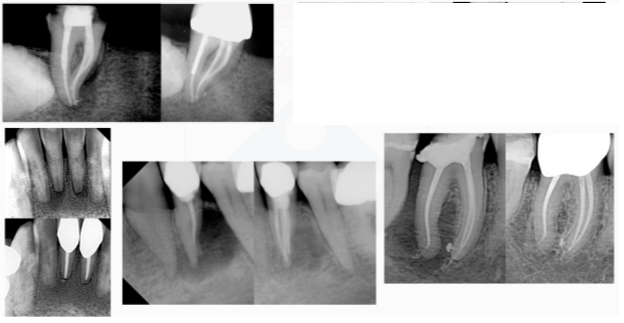

Figure 2: Sequential radiographs highlight the role of mechanical preparation and biological disinfection in achieving and maintaining periapical health.